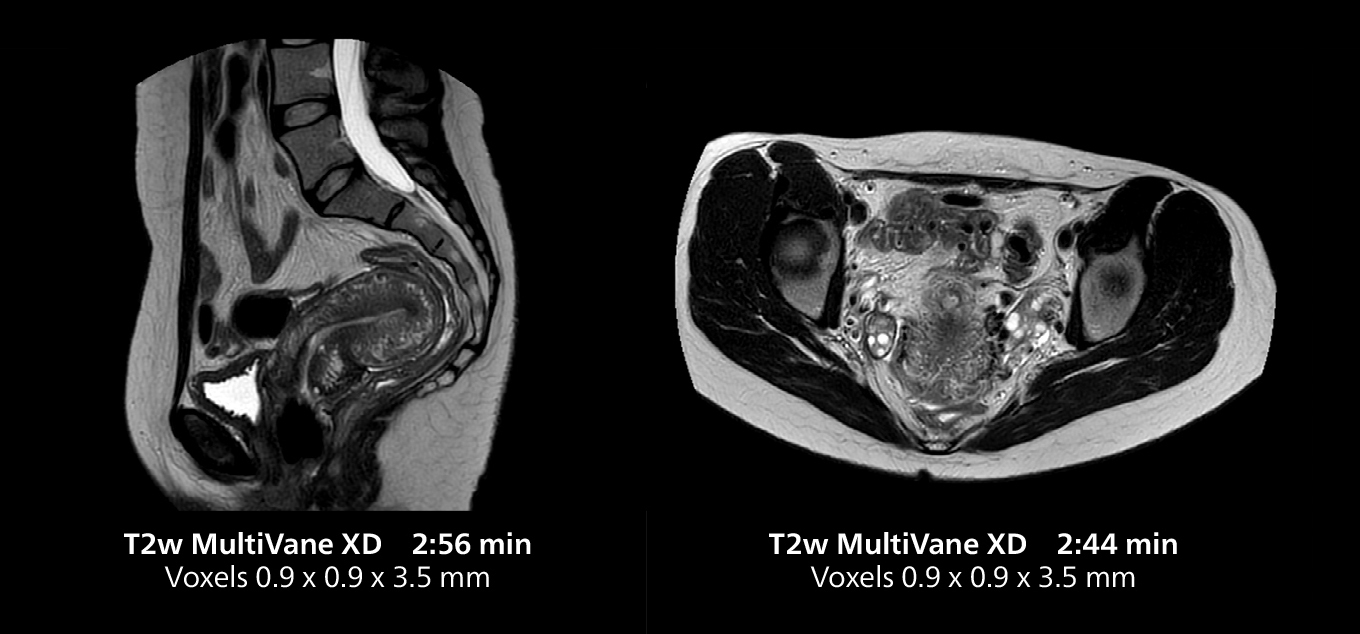

This MRI case illustrates good resolution and imaging quality obtained within reasonable scan times using the MR 5300 1.5T system with the anterior torso cardiac coil that allows use of a large field of view (FOV).

Dr. Gellée highlights the robust free-breathing scans as “the feature that makes the biggest difference in my daily work. The 3D free breathing sequences are very reproducible, and the axial acquisition is very good. For example, in endometriosis, which is one of my focus areas, it provides high contrast and good resolution so that I can see small details. We also use free breathing for liver and pancreas imaging. In multi-phase liver studies, 4D Free Breathing delivers 3-second temporal resolution, making a dynamic scan with more than one arterial phase possible.”

For elderly patients in particular, free-breathing protocols make exams more comfortable while providing the image quality needed for confident diagnosis. “We have a large elderly population in the city, and because long breath holds are difficult for many older patients, free-breathing is a significant advantage,” Dr. Gellée says. “In cardiac MR for example, with 4D flow and late enhancement, we get excellent diagnostic quality without asking our patients to hold their breath.”